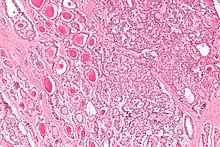

Micrograph of a strumal carcinoid. H&E stain.

The strumal carcinoid is a type of monodermal teratoma with histomorphologic features of (1) the thyroid gland and (2) a neuroendocrine tumour (carcinoid).[1][2]